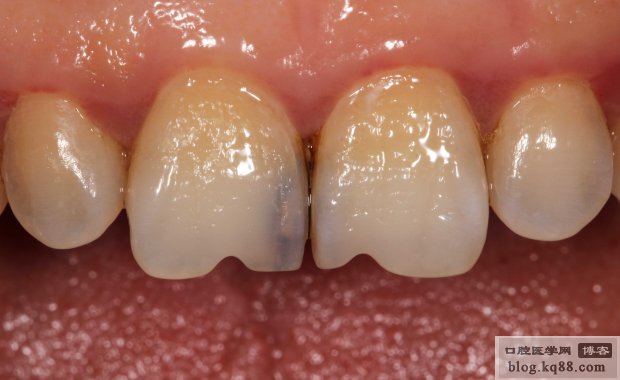

術(shù)前